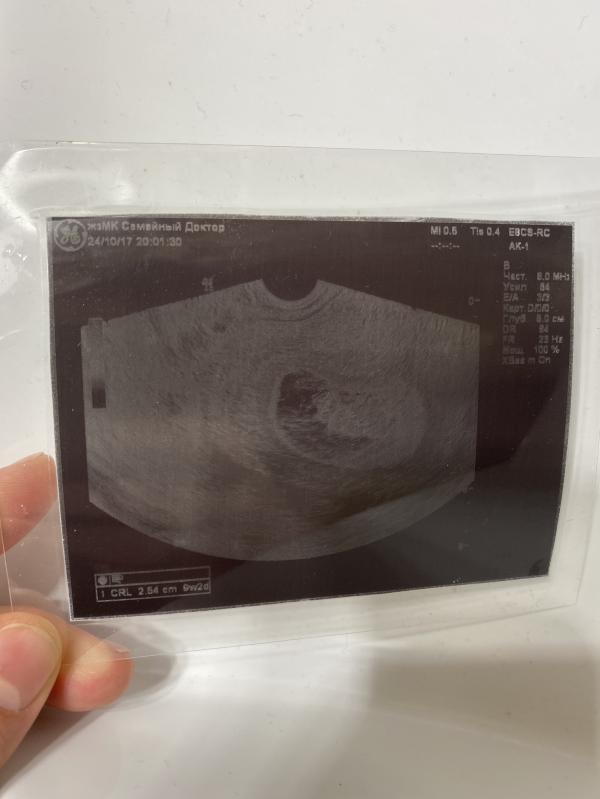

История о том, как я "запорола" картинку с УЗИ для детского альбома😹😹😹

Короче, там же бумага как чековая лента, ну, думаю, заламинирую, а то больно хлипкая - и хоть сохранится! Ага, лох это судьба, эта бумага при нагревании в ламинаторе темнеет😹 В общем, если соберетесь делать ТАК - сначала сделайте копию этой картинки с УЗИ на обычную бумагу, а потом уже в ламинатор. Или распечатайте из эл.карты сразу на обычную бумагу. Хорошо, что есть дуюликаты и эл.версия, а то моя "память на долгие годы" д...